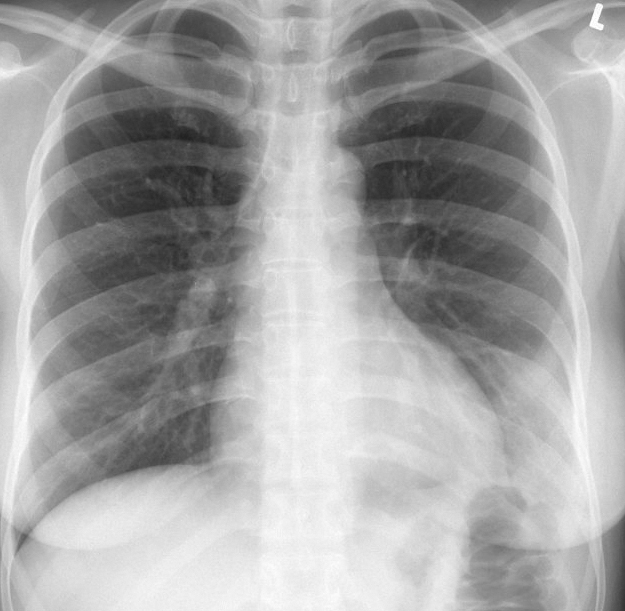

Case 12 antmed LLL pneum PA

Date: 04/17/2005